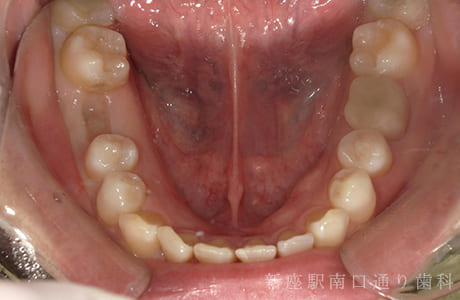

CASE.03

右下6番が破折抜歯後に

フルジルコニアブリッジで修復した症例

-

- 主訴

- 歯がないところを治したい

- 治療法

- 右下にフルジルコニアブリッジで修復

- 治療期間

- 1ヶ月半

- 費用

- ¥240,000(税込)

右下6番が破折し抜歯後にフルジルコニアブリッジで修復したです。

【リスク・副作用】

過度の咬合や衝撃で割れることがあります。治療直後は歯や歯茎に一時的な違和感や痛みが出ることがあります。